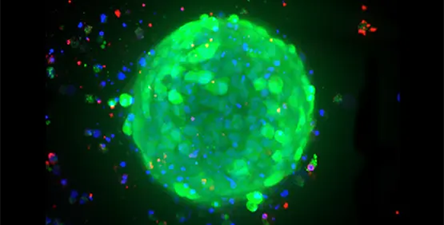

Breast cancer organoids

Image Credit: Molecular Devices UK Ltd

Breast cancer patients’ survival rates depend heavily on early identification and treatment. This involves the use of therapeutically relevant tumor models to better understand the mechanism, identify tumor biomarkers, and screen anticancer medicines. Breast cancer tumoroids provide a platform for investigating tumor physiology and response to targeted therapy.